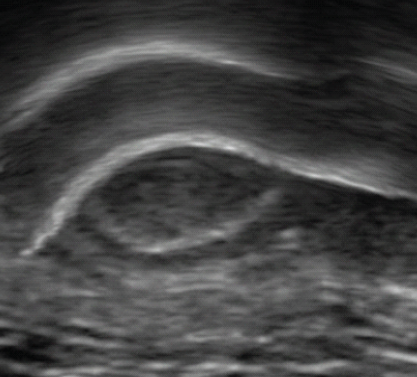

CBCT images were evaluated systematically the following changes of the bones: (1) cortical erosions, which are discontinuity or irregularity of cortical bone surface, a measure that was 0.1 mm or more, (2) osteophytes, which are bone outgrowths or excrescence of the articular surface, (3) subchondral cysts, which are well delimited areas of radiolucidity in the subchondral bone, (4) condylar flattening measured qualitatively, and (5) joint space width (Fig. 1).

Figure 1: Temporomandibular joint cone-beam computed tomography section for the evaluation.